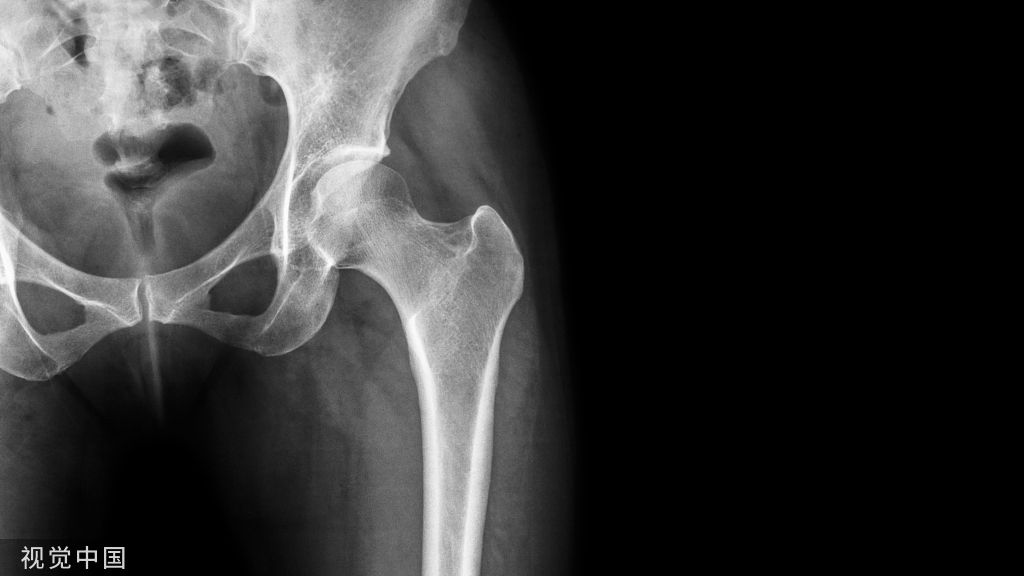

痛风是一种单钠尿酸盐沉积所致的炎症性疾病,以急慢性关节炎为特征。如果患者不进行治疗,痛风症状可持续数天甚至数周。此外,除无症状的“非急性间歇期”外,痛风的发作频率和严重程度将随着时间的推移而逐渐增加大约有15%的痛风患者疾病可进展为晚期痛风,其特征是痛风石沉淀形成皮下结节,并带来持续性关节炎症及潜在关节侵蚀/畸形风险。

值得关注的是,近几十年来,痛风的发病率在全球不断升高,目前已经成为一种威胁人们健康和生活质量的重要疾病。最新的流行病学调查显示,美国有近3.9%的成年人(>20岁)诊断出痛风,而中国成人近10年的痛风发病率也高达0.86%~2.20%。